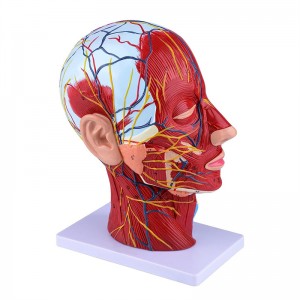

【1: 1 I-Lifesise】 Ingxenye ye-Median ye-Median ye-1: 1 yemvelo enkulu yemvelo & imodeli yemisipha yemisipha ye-nearal ye-nearal ye-nearal (uhlangothi olungakwesokudla). Umsebenzi omuhle. Ukunikeza uhla oluphelele lwezici ze-anatomical.

Le modeli iyinhloko enkulu yemvelo nemodeli ye-neurovascular yemisipha eyindilinga, isakhi esingu-1, ekhombisa imininingwane yekhanda lelungelo lomuntu kanye nentamo kanye nengxenye ye-Median Sagittal, okubandakanya imisipha engemihle yobuso, imithambo ephakeme yobuso obukhulu bobuso kanye nesikhumba, izinzwa nokwakheka kwempilo kwe-parotid gland kanye nepheshana lokuphefumula elingaphezulu, kanye nesakhiwo seSigaba se-sagittal somgogodla wesibeletho